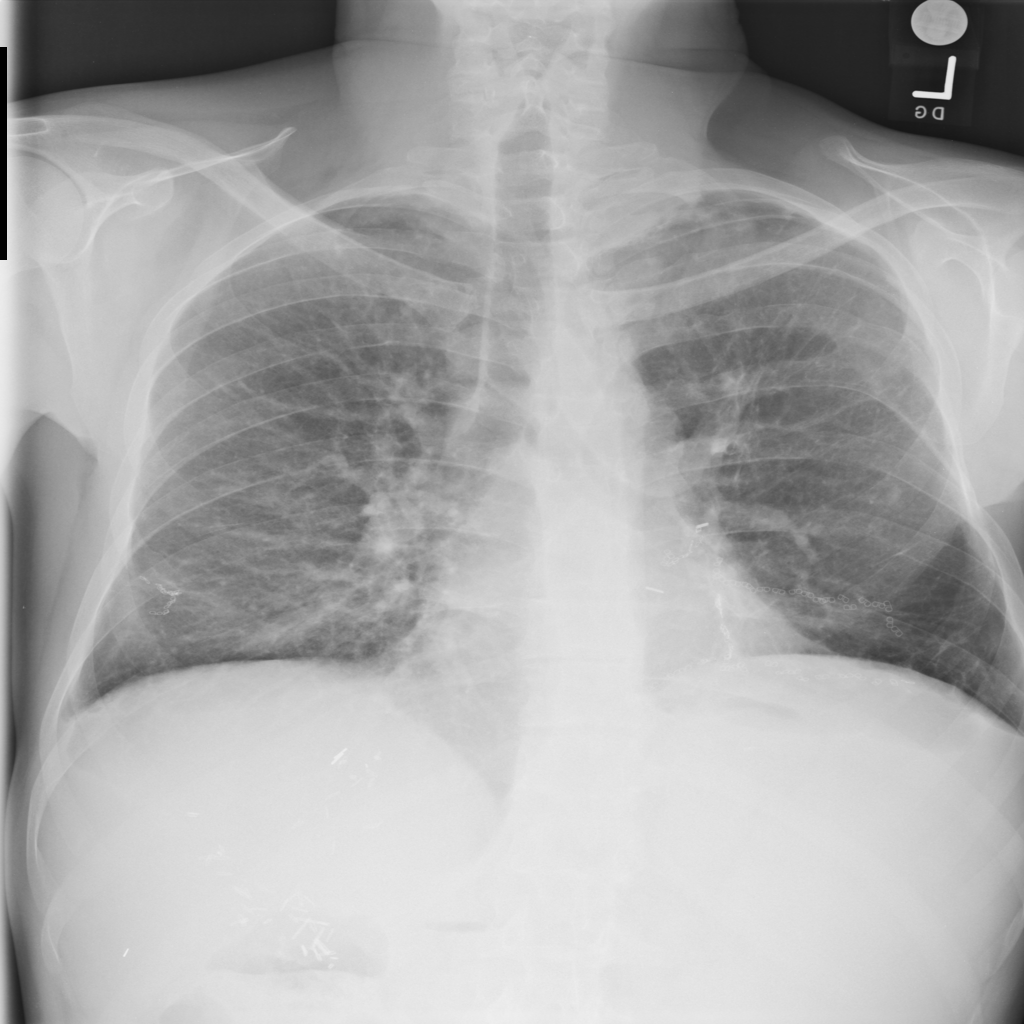

Showing up to 90 reference images for Nodule.

PAT-F3E7 · IMG-002Nodule

PAT-F3E7 · IMG-002

PA